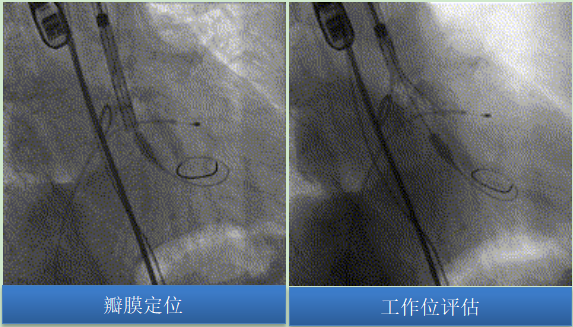

主動(dòng)脈根部造影可見主動(dòng)脈瓣少量反流,綜合術(shù)前討論竇部結(jié)構(gòu)、左冠風(fēng)險(xiǎn)預(yù)估,采用20mm球囊預(yù)擴(kuò),可以對(duì)瓣膜開放程度及選瓣做正確的指導(dǎo)。術(shù)中未見腰征,無(wú)造影劑滲漏,左右冠顯影良好。

圖片

預(yù)裝TaurusEliteAV26瓣膜,輸送系統(tǒng)順利過(guò)弓、跨瓣,初始于瓣環(huán)平面0mm精準(zhǔn)定位釋放,釋放過(guò)程中瓣膜錨定穩(wěn)定,未下滑。

依據(jù)CALM原則,予多角度評(píng)估瓣膜后,將瓣膜脫鉤釋放。